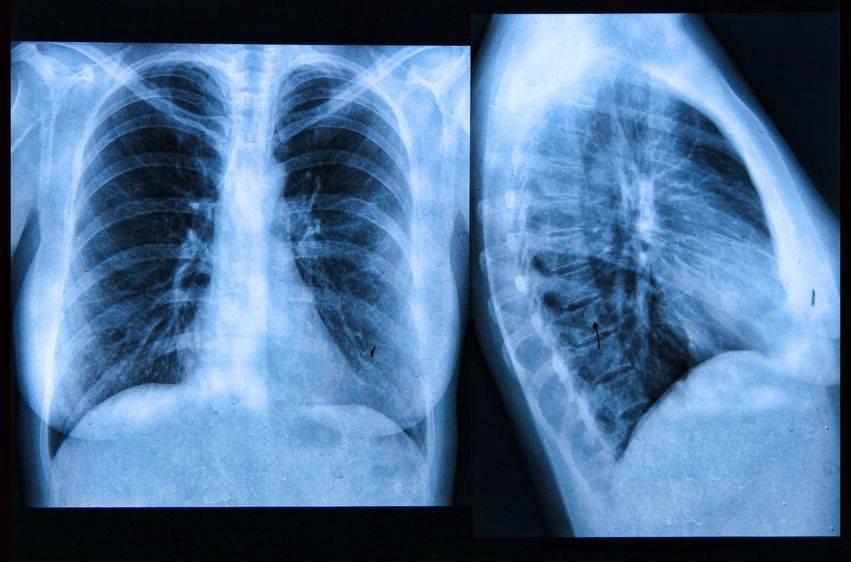

临床挑战:哮喘患者突发胸痛,原因为何?

哮喘突发胸痛,疾病又添新症。一个胸痛症状,且看诊断流程。 病例分析 一、确诊哮喘患者,突然出现胸痛 患者,女,49岁,因反复喘息17年,加重伴呼吸困难10小时急诊入院。入院查...